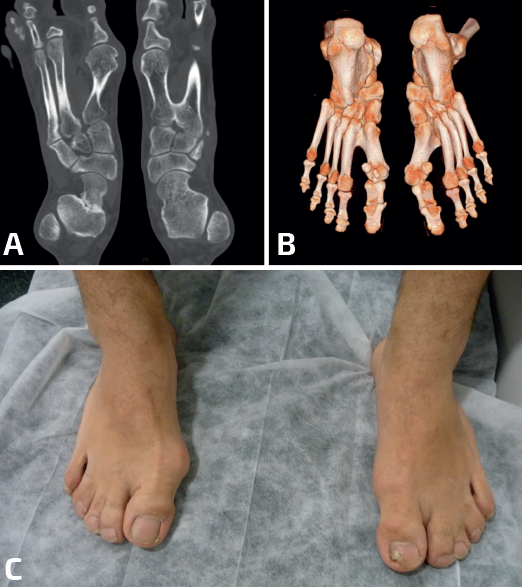

- Múltiples/Masivas: las coaliciones tarsales múltiples/masivas (dos o más de dos en el mismo pie) pueden presentarse como casos aislados no sindrómicos o asociados a otros problemas dentro de un síndrome (Figura 4). Se han descrito casos no sindrómicos de coaliciones combinadas calcaneonavicular, talonavicular y talocalcánea, con frecuencia bilaterales(26,50), y también afectando a la articulación tarsometatarsal(51). La mayoría son asintomáticas y algunas cursan con inestabilidad y entorsis de repetición en el paciente adolescente(50). En algunos casos observamos que la clínica depende del desarrollo de reacciones de estrés en los huesos limítrofes, como en el caso de un paciente con coaliciones tarsales talocalcáneas y naviculocuboideas y con dolor en la cuña intermedia(52). Aunque la mayoría mejoran con tratamiento conservador, existen casos publicados con cirugía de resección con mejoría de los síntomas(50,53,54,55,56,57). En muchas coaliciones múltiples/masivas del tarso, el tobillo (tibiotalar) tiene que adaptarse para poder trabajar como una tibiotalar y una subtalar a la vez, lo que conlleva un crecimiento adaptado a la función, formándose un tobillo cóncavo-convexo (ball and socket en la literatura anglosajona)(58)(Figura 5). En la mayoría de los casos, el hallazgo es casual y el paciente está asintomático. En línea con otras coaliciones, en los pacientes sintomáticos la clínica deriva de un pie plano-valgo. Las soluciones mecánicas consisten en el uso de plantillas con un buen gradiente supinador o en una cirugía de realineación mediante una osteotomía supramaleolar de cierre con base medial(59,60). En algunos pacientes con artrosis subtalar o tibiotalar avanzadas, los procedimientos de realineación pueden combinarse con artrodesis(61,62).